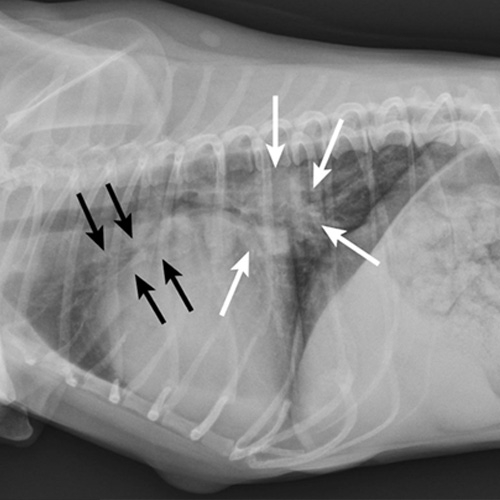

Figure 1.

Right lateral thoracic radiograph of a dog that was presented with labored breathing and a moist cough. The patient had a history of a heart murmur, and the breathing pattern was synchronous with increased effort on inhalation. Thoracic auscultation revealed diffuse, soft moist crackles and a 4/6 left systolic heart murmur over the mitral region. Butorphanol and furosemide were administered and the patient was allowed to rest with supplemental oxygen before radiography. Radiographs showed a VHS of 12.5, significant left atrial enlargement (white arrows), and pulmonary venous distension (black arrows) consistent with left-sided heart failure. Mitral valve insufficiency caused by valvular endocardiosis was confirmed with echocardiography.